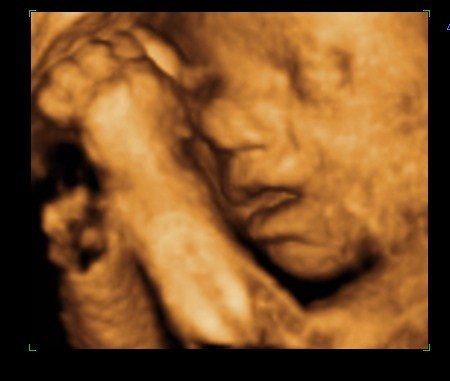

Efterfølgende er det bare blevet mere og mere omfattende for hver ny undersøgelse og scanning. I uge 10 var vi til genetisk rådgivning, da Mortens faster mangler hænder og fødder - det samme gør hendes datter. Allerede her var det lille hjerte blevet til en lille menneskefigur med boksehandsker ;o) I uge 12 var vi til NF-scanning og alt så godt ud. Igen så de efter hænder og fødder og alt var fint. Lav risiko for DS og fin baby. I uge 17 er vi til kønsscanning på en privatklinik og får at vide, at vi venter en lille pige. Fik set hende i 3D og tænk at der var sådan en fin lille en inden i min mave. Hun havde på dette tidspunkt ikke meget fedt på kroppen, så minder mest om en lille alien. Men hun er vores lille rumvæsen. I uge 19 er vi til MD-scanning og får at vide, at det er en fin lille baby, der har det godt og vokser som den skal. Hun lå med krydsede ben, så vi fik ikke bekræftet kønnet.

Jeg fik først "mave på" i uge 24, så for mig har scanningerne været guld værd - jeg kunne jo ikke se det udenpå i meget lang tid.